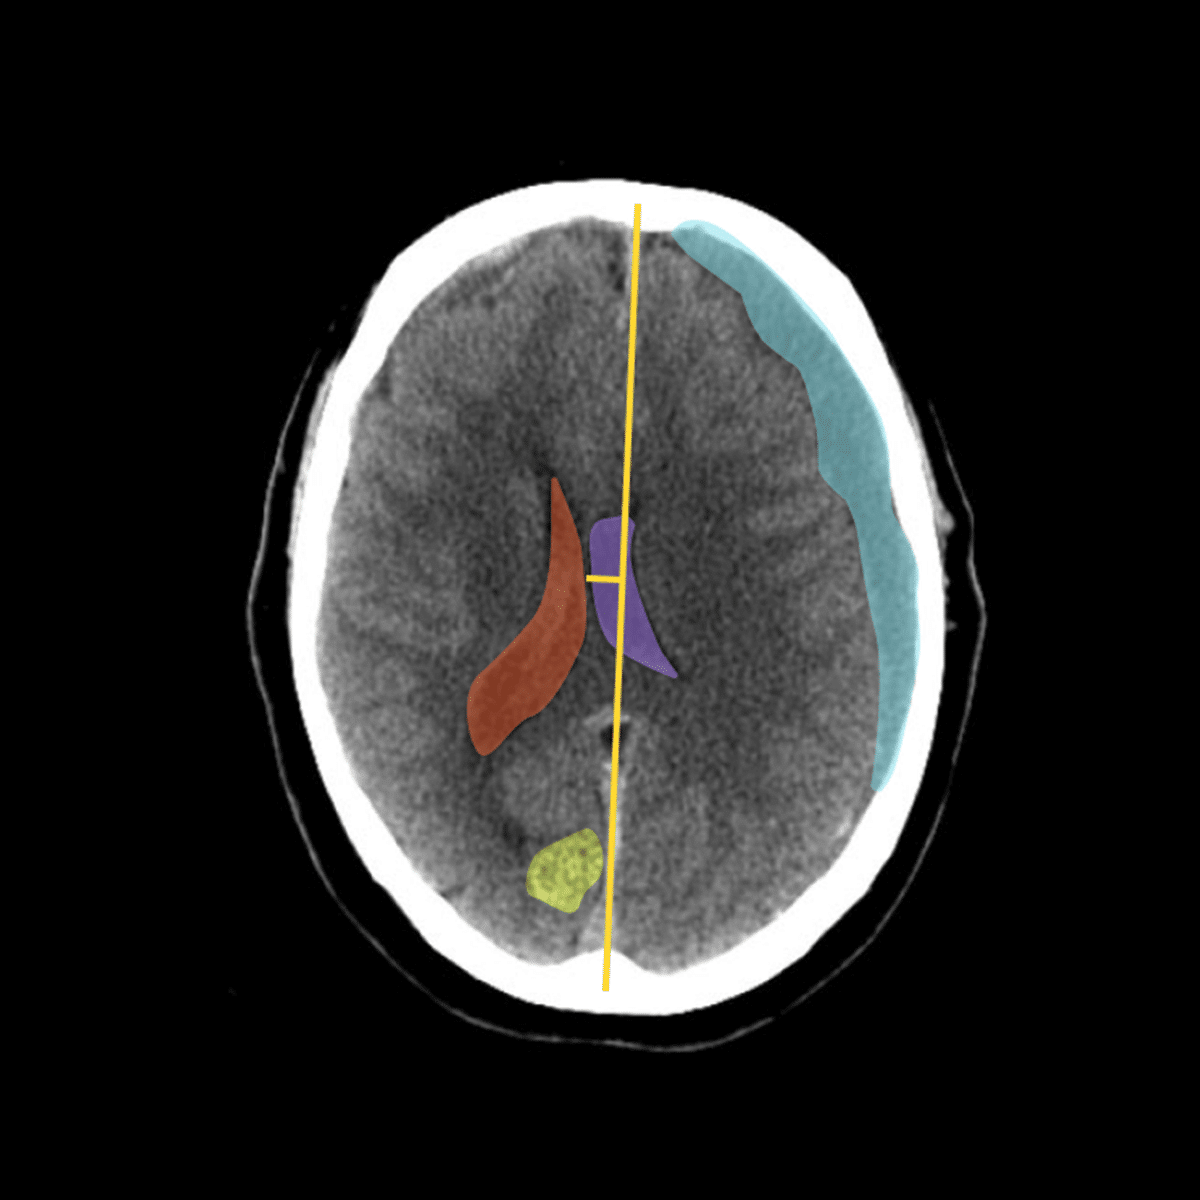

Viz ICH+, an AI-powered solution for measuring and segmenting hyperdense collections on non-contrast CT images. It includes color-coded overlays for...